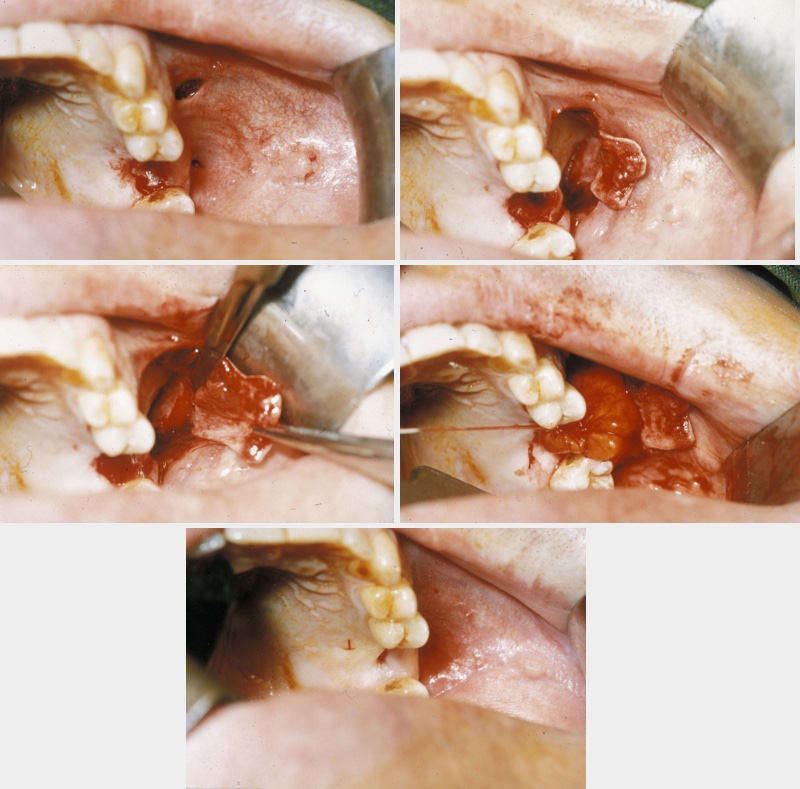

A combination of buccal fat pad and buccal advancement flap is probably the most effective way to close an oroantral fistula. The advantage of the technique is that the vascularised buccal fat pad fills the defect below the buccal advancement flap. This provides mucosal closure and thereby creates a double-layered vascularised closure that virtually has no chance of dehiscence and breakdown. The technique is illustrated in Figure 5.

Figure 5: Top left: combination approach using the buccal fat pad and the buccal advancement flap technique; top right: flap elevated; bottom left: flap mobilised; bottom right: fat pad inset, mucosa partially advanced.